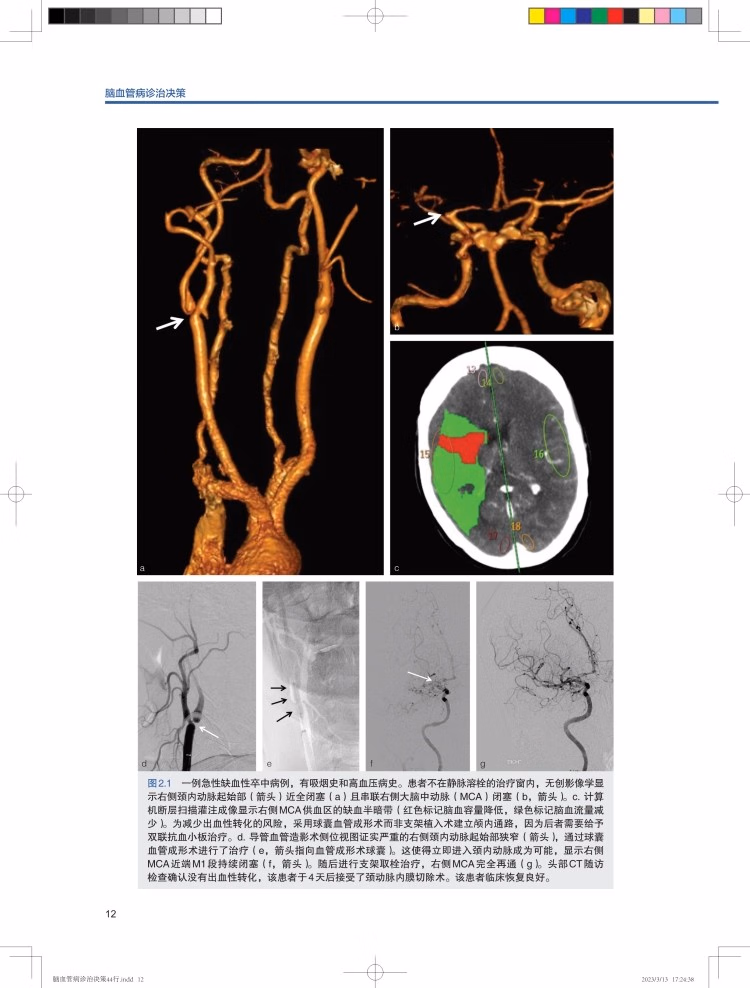

在线试读